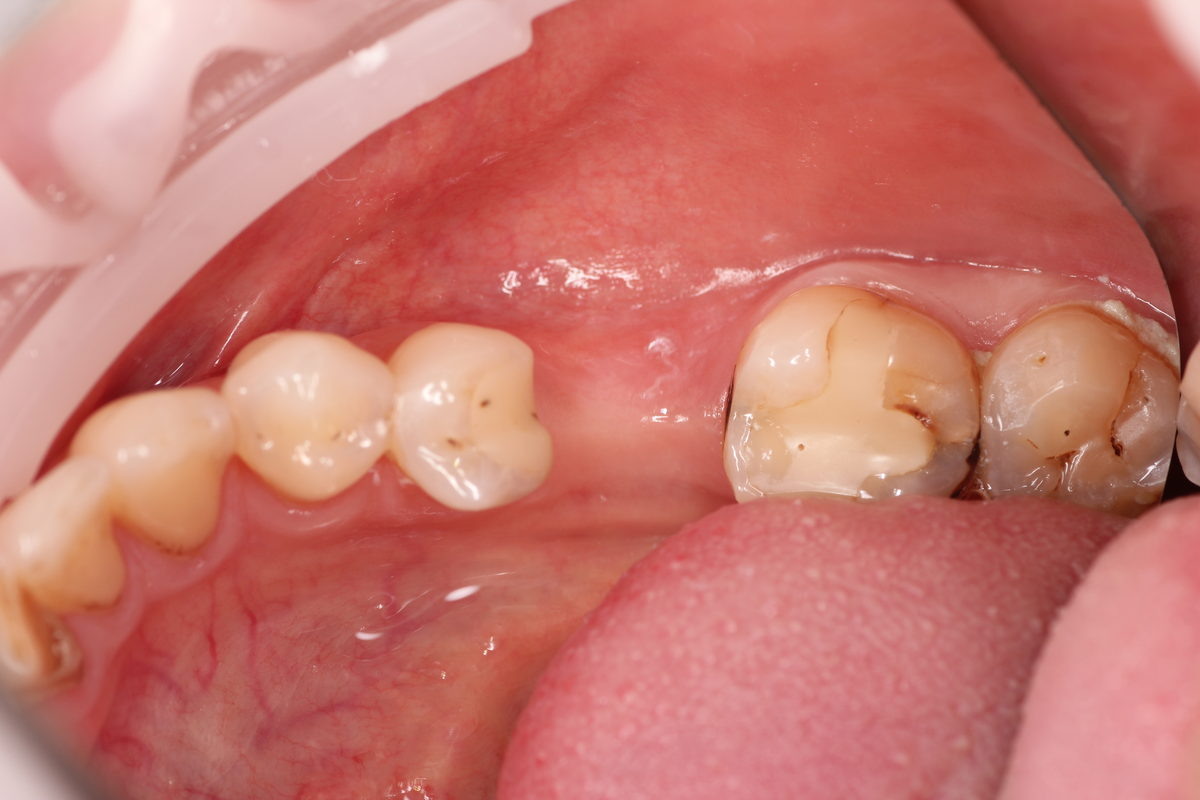

КЛИНИЧЕСКИЕ ПРИМЕРЫ СИТУАЦИЙ, КОГДА НУЖНА ПЛАСТИКА ДЕСНЫ 1. Простая имплантация при длительном отсутствии зубафото до импланатции фото после импланатцииУстанавливается имплантат, проводится НТР (направленная тканевая регенерация) с помощью сст (соединительнотканный трансплантат), устанавливается фдм (формирователь десны)

фото до импланатции

Атрофия слизистой со стороны щеки в связи с длительным отсутствием зуба, а так же с воздействием мышц щеки.

Для изготовления эстетичной и функциональной реставрации необходимо добавить мягкие ткани.